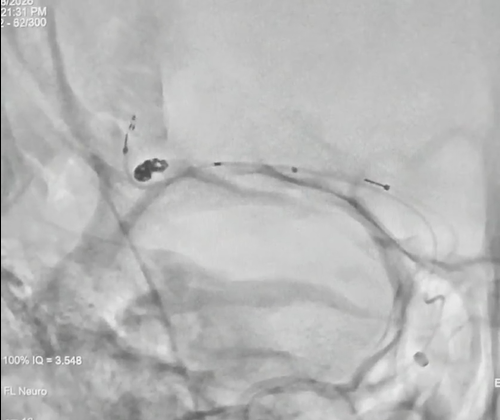

1. 术前评估,基线造影

DSA三维重建示:大脑中M2分叉部可见一动脉瘤,瘤体不规则

6. 警报解除,回归日常

术后DSA示:动脉瘤完全栓塞,瘤腔内未见造影剂充盈,载瘤动脉通畅